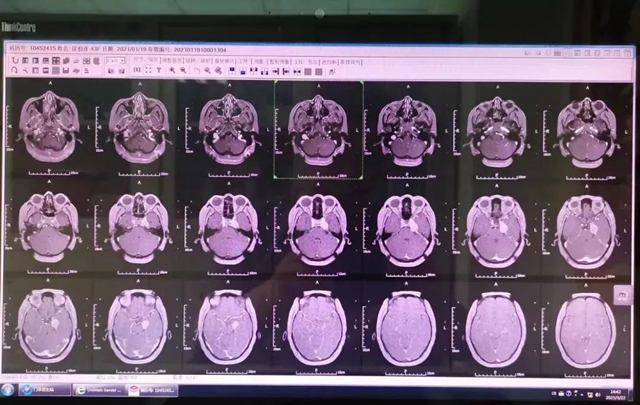

2022年,泸州泸县30岁的徐女士受头痛困扰已经半年多,头颅核磁共振检查发现左侧岩尖区占位性病变,因惧怕手术多方辗转求治来到神经外科。

“患者颅内肿瘤体积较大,具有手术指征,但该肿瘤位于海绵窦区,与颈内动脉、三叉神经、外展神经、动眼神经等颅内重要组织结构关系密切,手术难以全切,术后并发症几率高。”

神经外科团队制定了详细的头部伽马刀治疗方案,通过精确的立体定向,整个治疗过程仅20分钟,无痛苦、无出血、无感染。

徐女士2天后顺利出院。近日,来院复查,颅内肿瘤明显缩小,症状、体征明显改善,效果极佳。